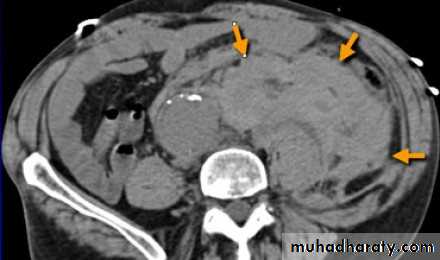

Ruptured abdominal aortic aneurysm